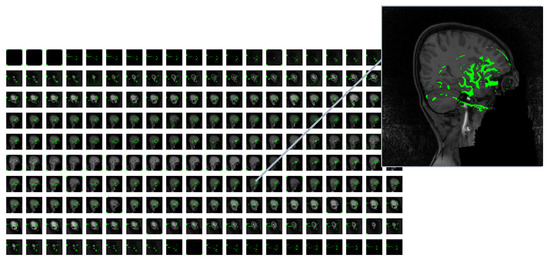

As mentioned earlier, we extracted 20 features for each slice of every MRI image within the ADHD-200 dataset. To provide clarity regarding the regions from which these 20 features were extracted, the class activation mapping (CAM) technique was employed. The CAM offers a spatial understanding of the CNN’s decision-making process, aiding in the interpretation and explanation of model predictions [25]. CAM is a technique utilized to visualize and comprehend regions of an input image contributing the most to the final prediction of a convolutional neural network (CNN). This is achieved by obtaining an activation map through the average across all channels, indicating the importance of each spatial location. The CAM results led us to identify high-level features, including anatomical structures indicative of ADHD. As shown in Figure 5, the heatmap highlights regions in the original MRI slice that contribute the most to the activation of the last convolutional layer in the VGG16 model. The heatmap is then overlaid onto the original image. In some black slices that extend to the original 3D MRI for the purpose of standardizing sample sizes, random heatmaps may be observed. However, in slices that represent actual brain slices, we generally observe discernible areas of the brain selected for further feature extraction steps. It is important to note that this sample selection was performed at random within the entire dataset. To standardize input dimensions across subjects, black slices were added only when the original MRI volume contained fewer than 200 slices. These zero-intensity slices were symmetrically padded at the beginning and end of the volume to avoid disrupting the anatomical structure. Since these slices contain no relevant information, they are effectively treated as non-informative during training. This is further supported by CAM visualizations, which show no meaningful activation in the padded regions, confirming that the model focuses on actual brain tissue. Additionally, normalization and dropout layers help minimize the risk of these black slices interfering with feature learning.

Figure 5. Visualization of feature activation using VGG 16-based class activation mapping (CAM) on MRI slices. The overlaid heatmap highlights regions of high significance, revealing key structures contributing to the neural network’s feature extraction.